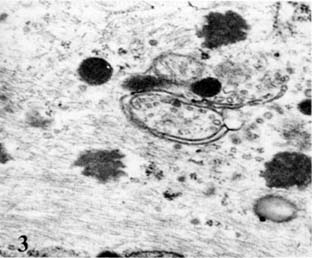

Β) Τόσο εντός των κυττάρων όσο και εντός των προσεκβολών παρατηρούνται πολυάριθμες νευρογλοιακές ίνες που σχηματίζουν πυκνές δέσμες και αποτελούν το παθογνωμονικό κριτήριο των αστροκυττωμάτων (Εικ. 1).

Ε) Τα νεοπλασματικά κύτταρα παρουσιάζουν κατάτμηση των μικροσωληναρίων ενώ τα διάμεσα ινίδια εναποτίθενται σε παράλληλες δέσμες. Φέρουν δε σπανίως πινοκυτταρικά κυστίδια στην ελεύθερη επιφάνειά τους. (Εικ. 2, 3).